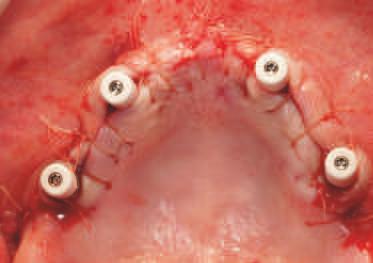

Implantur le subper ostale sunt structur metal ce fabr cate nd vdual pentru a se adapta ș a restab l zonele edentate. Personal zate ș concepute pentru a se potr v morfolog e osoase un ce a pac entulu , mplantur le subper ostale sunt plasate sub per ost ș sunt stab l zate pr n șurubur de f xare care ntră în contact cu osul sub acent ș țesutul f bros care le acoperă. Spre deoseb re de mplantur le convenț onale, mplantur le subper ostale se sprj nă d rect pe os ș prez ntă bontur care emerg pr n țesutur le g ng vale pentru a acomoda proteze f xe sau detașab le totale sau parț ale (un exemplu de implant subperiostal individualizat este ilustrat în fig. 6-14)

În z ua nserăr , după ce s-a real zat o expunere suf c entă a suportur lor anatom ce sub acente, mplantul este ver f cat în pr v nța adaptăr corecte, ar or ce mod f căr necesare sunt efectuate îna nte de plasarea f nală. Implantul este stab l zat pe poz ț e cu șurubur monocort cale nserate pr n găur predef n te în osul sub acent. Lamboul este decolat ș d secat corespunzător pentru a obț ne suf c entă pas v tate care să as gure o înch dere pr n ntenț e prmară în jurul bontur lor expuse ale mplantur lor. După per oada necesară de v ndecare, se au amprentele corespunzătoare pentru fabr carea ș l vrarea proteze f nale.